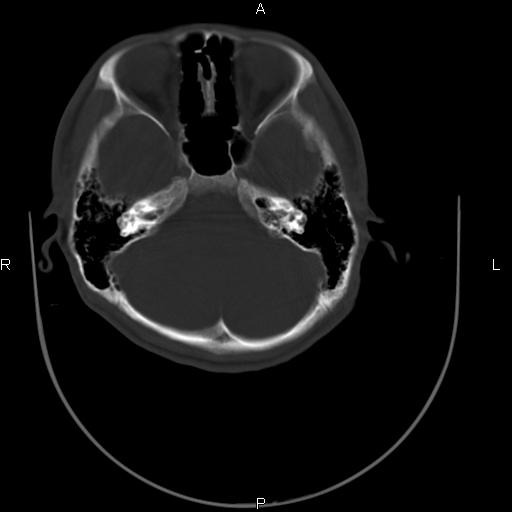

标题: CT27115:大家看一看,这孩子的颅骨表现? [打印本页]

标题: CT27115:大家看一看,这孩子的颅骨表现?

两名中学生打架,脑质内未见异常,未上传。

两例——颅骨结构正常,未见明显骨折征象。

感觉第2个颅缝密度高,额顶部板障有点厚,正常变异?地中海贫血?

以下是引用37度在2010-6-15 19:31:00的发言:[br]感觉第2个颅缝密度高,额顶部板障有点厚,正常变异?地中海贫血?